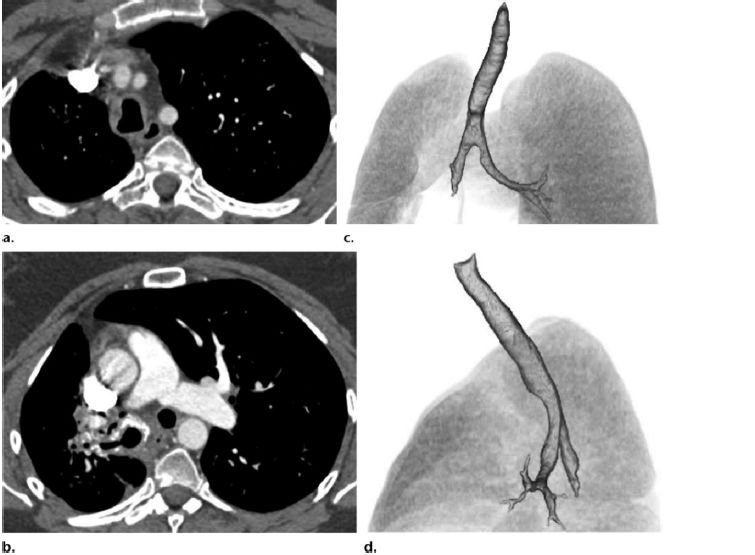

纵隔淀粉样变性常见于系统性淀粉样变性并可能由多个位置的肿大淋巴结构成,或者累及更广的范围。孤立的肿瘤样病变或者淀粉样瘤可能发生于任何的纵隔隔室。症状取决于病变的位置和临近受累结构。纵膈疾病常常表现为无症状的淋巴结肿大,这是除了气道疾病和结节实质疾病以外的第三常见的胸部表现(图5a,6,10)。纵隔淋巴结肿大可伴有多种钙化表现形式,包括点状,弥漫性,或蛋壳样表现。

图10 (a)图4的患者,CT平扫图像显示纵隔淋巴结肿大(a 和b箭头)静脉注射造影剂后淋巴结强化